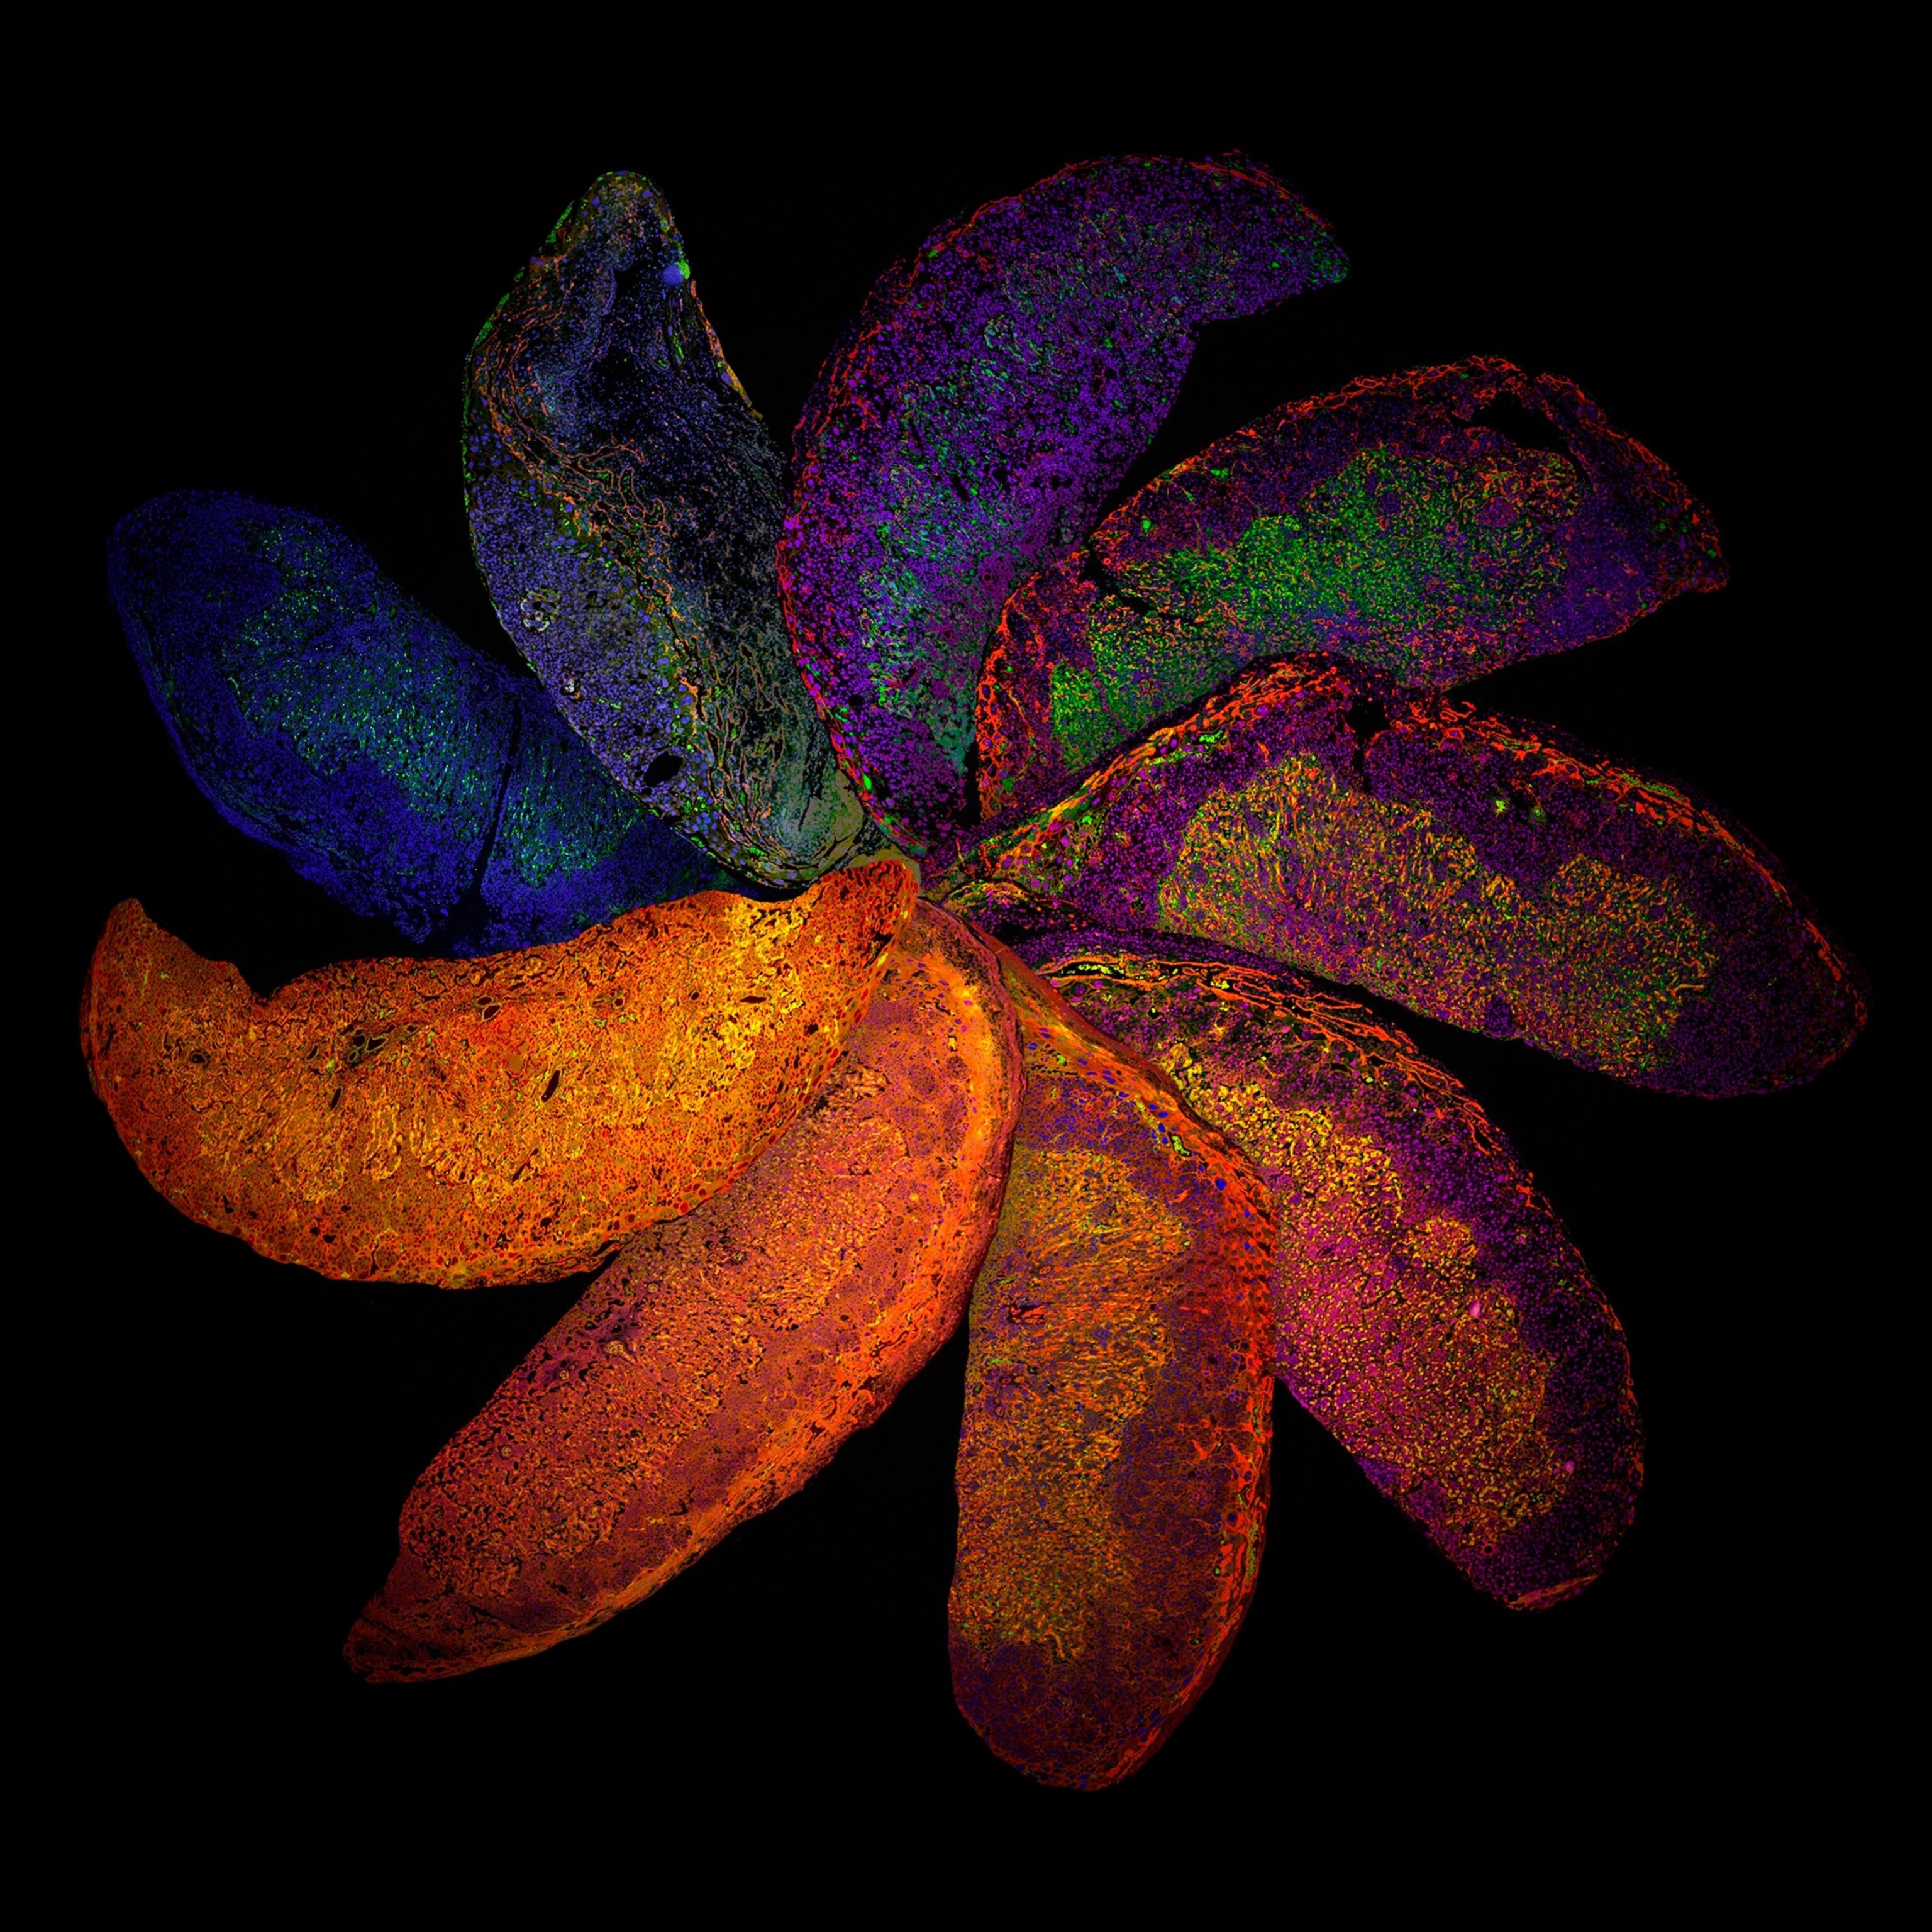

This year's submissions included mediums such as photography, illustrations, super-resolution microscopy, and medical scans.

Nine judges selected a total of 22 images to recognize for their achievements in creating imagery that displays scientific ideas as art. Wellcome Images also partnered with the Koch Institute for Integrative Cancer Research to share and source their pool of submissions.